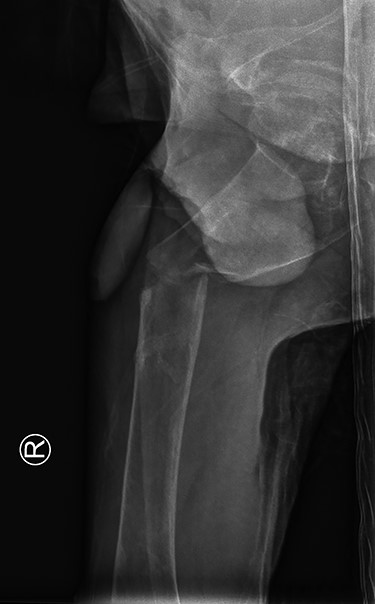

The patient was haemodynamically stable at presentation. He complained about pain in his right hip and was not able to move his right leg due to the pain. The patient was previously diagnosed with the renal Fanconi syndrome and had a previous collum femoris fracture on the left side. Conventional imaging revealed a subtrochanteric femoral fracture (Figs 1 and 2). Furthermore, contralaterally placed cannulated collum femoris screws and a severely decreased bone quality was found. No other traumatic injuries were present. Biochemical analysis showed a hypokalaemia of 3.0 mmol/l (3.5–5.0 mmol/l) and a mild hyponatraemia of 134 mmol/l (135–145 mmol/l). These findings can be related to the Fanconi syndrome.

Anterior-posterior view: right-sided subtrochanteric femoral fracture, left-sided collum femoris screws.